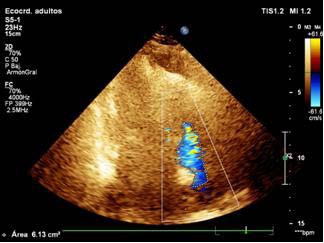

Imagen 3: Ecocardiograma doppler color, vista en 4 cámaras desde el ápex, precisando yet de insuficiencia tricúspidea (613 mm2) por repercusión sobre cavidades derechas de la hipertensión pulmonar (HTP).

Conclusión: Estenosis Mitral Severa. Hipertensión Pulmonar (HTP) Severa secundaria a valvulopatía mitral. Disfunción de Ventrículo derecho Sistodiastólica.